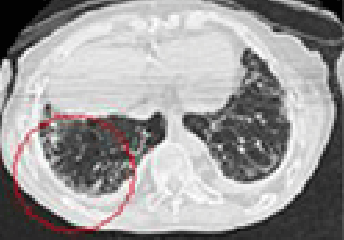

석면폐증(잠복기 약 15~40년)

잠복기가 약 15~40년에 걸친 석면으로 인한 석면폐증에 대한 CT사진

석면에 의한 폐 조직에 상처로 나타나는 폐섬유화 증상

• 폐의 섬유화로 희게 나타나며 공기집이 생겨 벌집모양으로 나타남

석면폐증의 병 유형(의심형, 초기형, 진행형) 및 폐기능 장해단계(정상, 경도장해, 고도장해)에 따라 1~3급으로 구분

• 석면폐증의 병 유형 : 폐섬유화 소견에 따라 의심형, 초기형, 진행형으로 구분

폐섬유화 소견에 따른 의심형 이미지 〈의심형〉

폐섬유화 소견에 따른 초기형 이미지 〈초기형〉

폐섬유화 소견에 따른 진행형 이미지 〈진행형〉